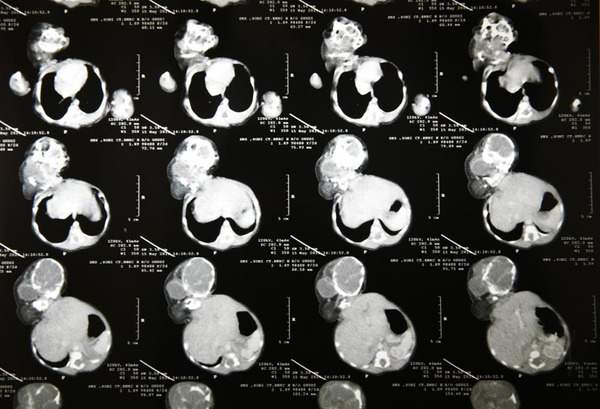

据报道,这名女子叫阿穆雷克·拜尔瓦(Amlekha Bairva),现年22岁。4月份时,拜尔瓦在村中政府公立小医院中生下一名怪婴。这名女婴体重约2公斤,属于寄生双胞胎。她的双胞胎姐妹已经部分成形,头部通过脖子长在其肚子上。